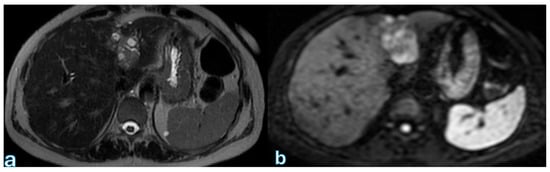

To assess hepatic perfusion anomalies and detect vascular pathology, contrast-enhanced CT (CECT) and MRI (containing arterial and portal venous phases) are essential. Wedge-shaped regions of decreased enhancement, which are usually well-defined and free of mass effect, are imaging characteristics of hepatic infarction (Figure 6).

Infarcted areas show up as slightly hyperintense on MRI T2-weighted imaging (T2WI), which is indicative of ischemia or edematous alterations.

In addition to identifying infarction, CT and MRI can detect underlying vascular abnormalities that cause hepatic ischemia, such as portal vein thrombosis, hepatic artery thrombosis, and hepatic or celiac artery injury/dissection. Furthermore, patients may be at risk for postoperative hepatic infarction if they have pre-existing vascular disorders such as mesenteric vasculitis, median arcuate ligament syndrome, fibromuscular dysplasia, or significant atherosclerotic disease, especially near the celiac artery origin. Preoperative vascular imaging should be thoroughly examined to identify high-risk patients and foresee probable postoperative problems due to the possibility of hemodynamic instability or infection.

On contrast-enhanced imaging, splenic infarction is radiologically represented as a wedge-shaped, non-enhancing area, with its base along the splenic capsule and its tip pointing toward the splenic hilum (Figure 7).

Over time, these infarcts may completely resolve or result in progressive splenic atrophy due to fibrotic contraction of the infarcted tissue. Early radiologic identification of splenic infarction is essential to ensure appropriate clinical monitoring while avoiding unnecessary interventions in asymptomatic patients.